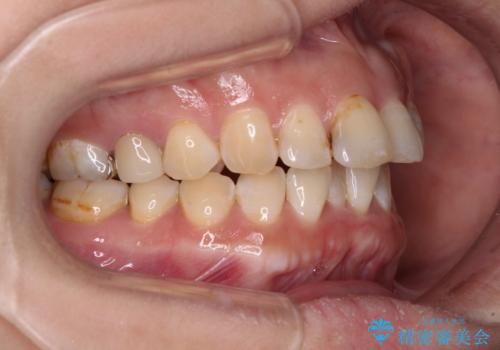

- 飛び出た上の前歯を気にして来院された患者様です。

奥歯の咬み合わせは、上顎歯列が理想的な一よりも数mm前方にある状態でした。

なるべく早めに治療を終えたいとのことで、補助装置を用いて上顎臼歯を後方に移動させ、同時にワイヤー装置にて整えることとしました。